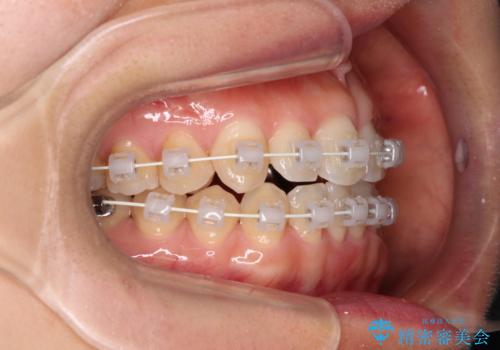

- 審美装置

装着されているブリッジを切断して矯正治療を行うことや、手間をかけずに早めに治療を終えたいとのことで、目立たないワイヤー装置による矯正治療を行うこととしました。

矯正治療中に上下前歯が接触しない時期があり、咬み合わせ改善のために期間がかかるのではないかと懸念されましたが、結果的には補綴治療も含めて1年以内の短期間で終えることができました。